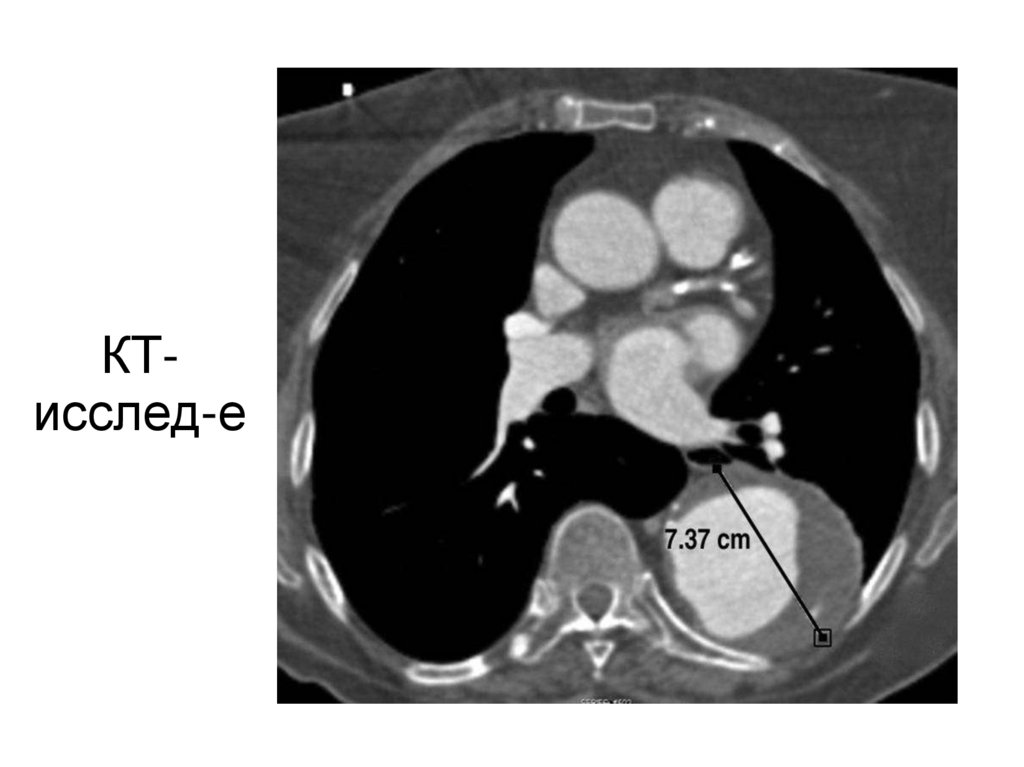

27. КТ-исслед-е

КТисслед-е